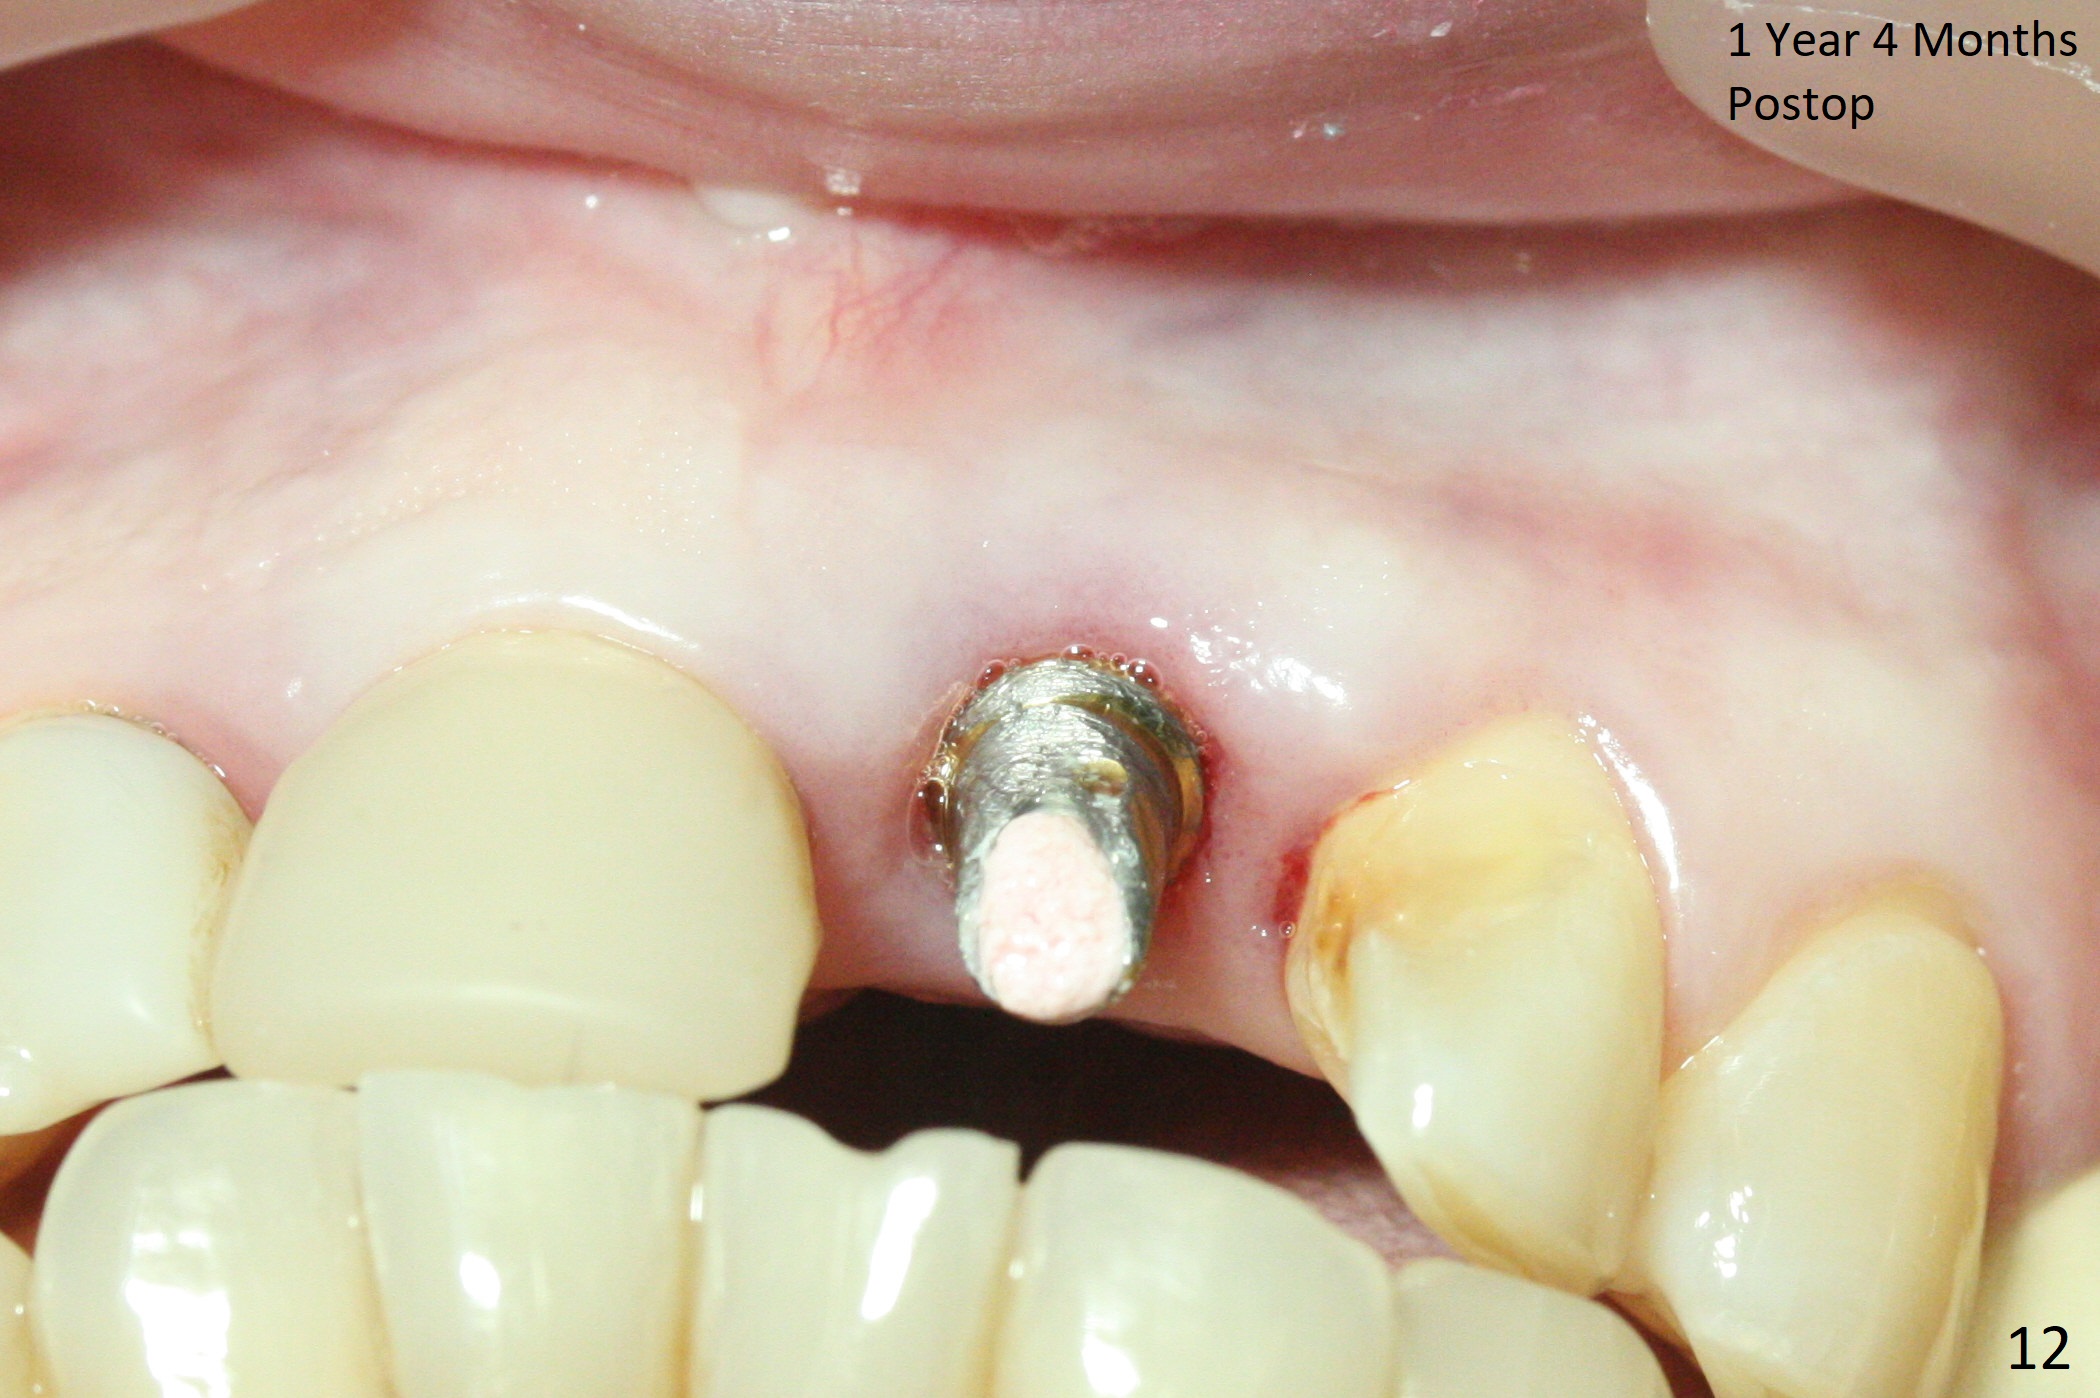

In spite of the incisobuccal shift of the tooth #9 with gingival recession (Fig.1) and loss of the buccal plate (intraop finding), there is no buccal contour collapse (Fig.2 *), due to the presence of the buccal bone of the neighboring teeth and the root of the affected tooth. After extraction, osteotomy (Fig.3) and dummy implant try in (Fig.4), a definitive implant is placed palatally with the buccal gap (Fig.5 *). In fact there is mild buccal contour collapse prior to bone graft (Fig.5 arrow). When allograft (Vera, Fig.6,7 *) is packed buccal to the implant and overlying abutment as a solid support, the buccal contour seemingly returns normal (Fig.6 arrowhead). An immediate provisional is fabricated to prevent loss of the bone graft during healing period. Bone graft kept in place by the provisional turns yellow 6 days postop (Fig.8). The buccal plate remains strong, while the fistula becomes indistinguishable. After adjustment of the provisional margin a few times (nearly 3 months postop, Fig.9,10), the gingival margin appears to have grown incisally, as compared to Fig.1. There is minimal buccal bone collapse (Fig.10). Dislodgement of the abutment and provisional forces her to return 1 year 4 months postop; the socket has healed (Fig.11). The buccal plate is not concave 1 year 4 months postop (Fig.12). The gingiva is slightly recessive (Fig.13) with mild buccal plate concavity (Fig.14) immediately before cementation. The implant could be placed ~ 1 mm deeper (Fig.15).